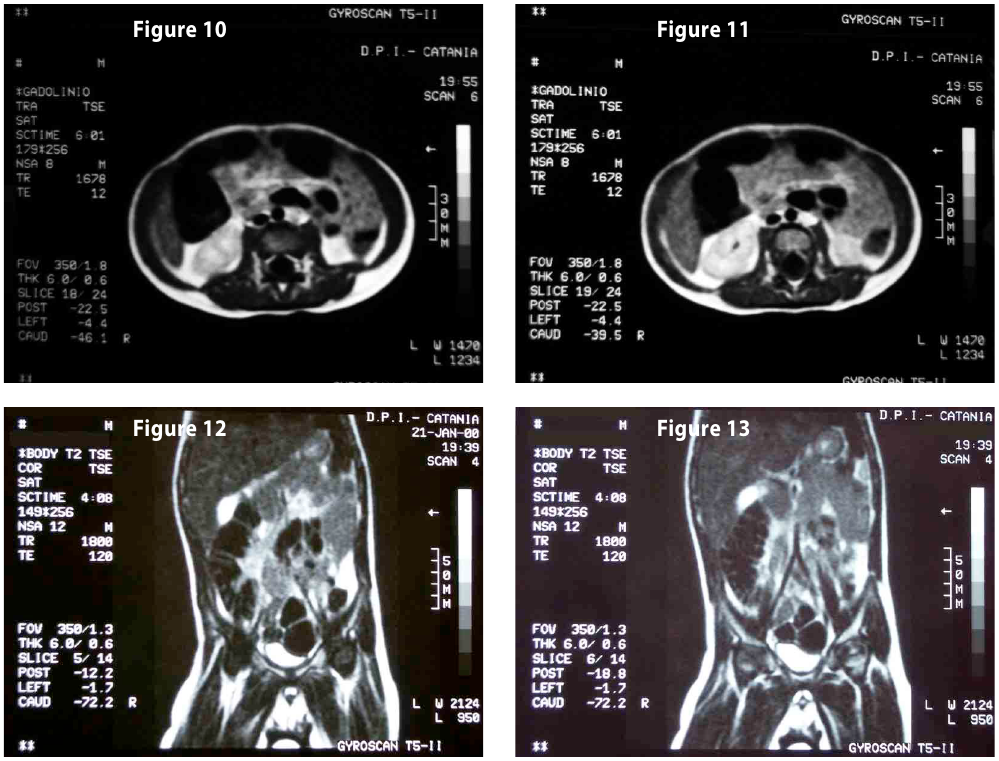

Complete objective response of neuroblastoma to biological treatment.

Figure12-13